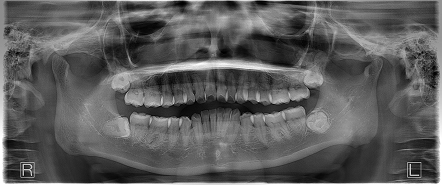

お口の中全体の写真

Before

- 上の左右と下の左右に親知らずがあり、インビザラインの治療前に親知らずの抜歯を行ってから矯正を行なったケースです。

咬合関係がⅡ級で咬合関係も治すなら右上第一小臼歯及び左上第一小臼歯の抜歯が必要でしたが、患者希望でそちらの抜歯は行わず、前歯を主に整えていくことになりました。

上の前歯の出っ歯以外にも上下の前歯に叢生を認め、咬合関係のズレも認めました。